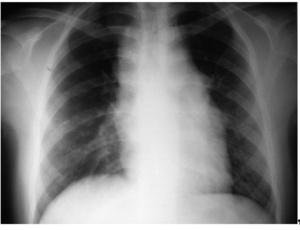

U większości pacjentów (około 80 proc.) choroba rozpoczyna się od jednostronnego powiększenia węzłów chłonnych w okolicy szyi (fot. 1). W 60 proc. przypadków stwierdza się powiększenie węzłów chłonnych śródpiersia, które u części chorych towarzyszy powiększeniu węzłów chłonnych szyi (fot. 2). Rzadziej zajęte są węzły chłonne pachowe i pachwinowe (30 proc.). Zmiany pozawęzłowe zlokalizowane są najczęściej w śledzionie (10-45 proc.), wątrobie (10-48 proc.), płucach (5-15 proc., najczęściej jako wynik szerzenia się ze zmian w śródpiersiu), kościach i szpiku (poniżej 5 proc.) i są objawem znacznego zaawansowania choroby.

W początkowej fazie powiększone węzły chłonne są zwykle niezbyt duże, twarde, niebolesne przy ucisku, bez odczynów zapalnych. W miarę rozwoju choroby zwiększa się ich liczba i wielkość oraz tendencja do przerastania i łączenia się w pakiety. Choroba szerzy się najpierw w układzie limfatycznym w sposób anatomiczny, zajmując kolejne grupy węzłów chłonnych, a następnie narządy pozalimfatyczne. Zajęcie węzłów chłonnych, śródpiersia i wnęk może powodować zajęcie płuc z następowym wysiękiem w opłucnej i osierdziu. Przy powiększeniu węzłów chłonnych przyaortalnych może dochodzić do nacieczenia śledziony, a następnie wątroby.